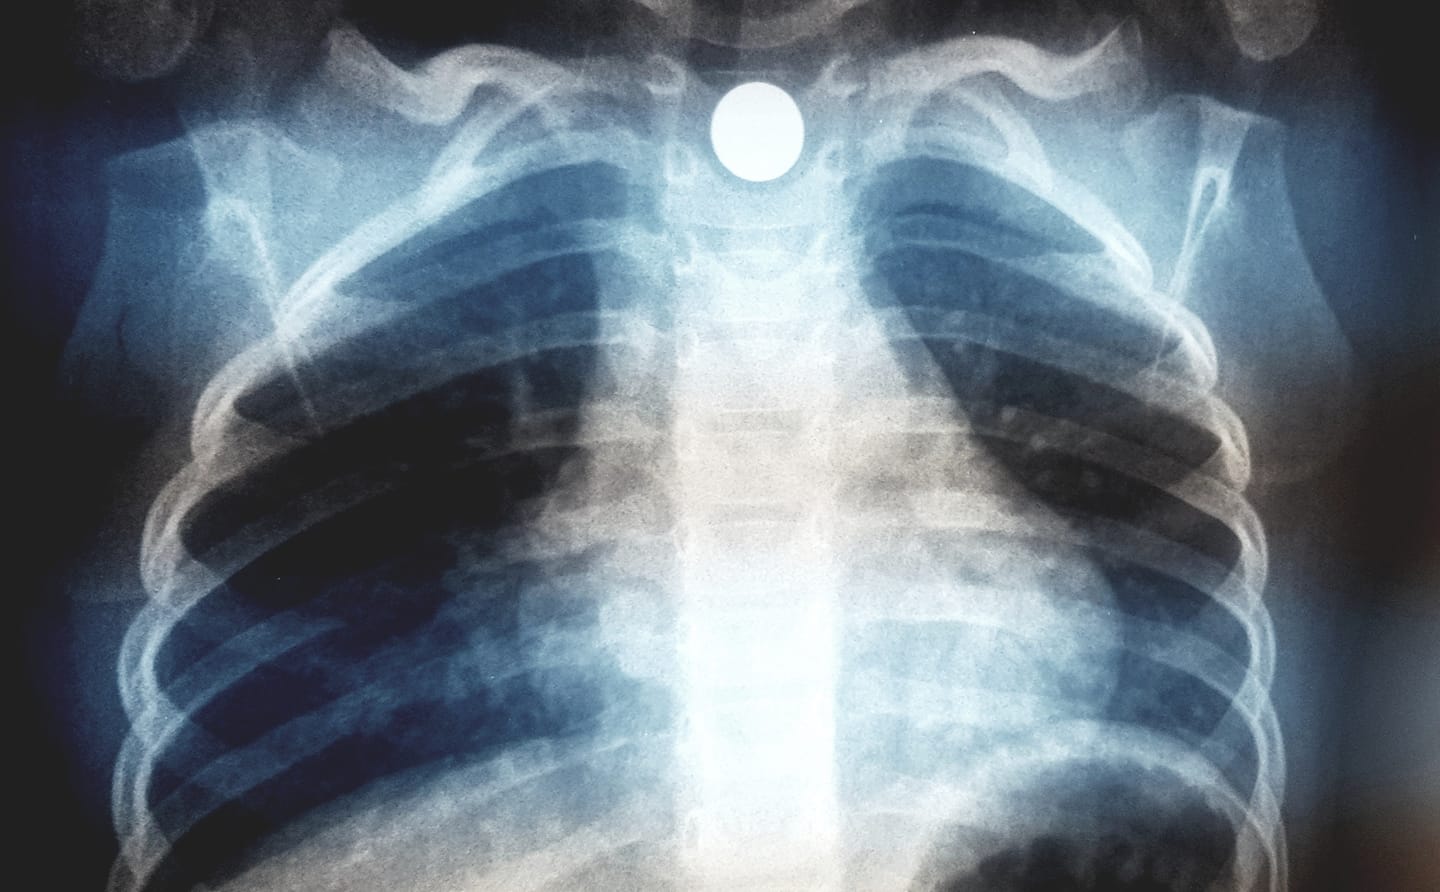

Με μια ανάρτησή του στο Facebook την οποία συνοδεύει και με μια ακτινογραφία θώρακος ο παιδίατρος Γιώργος Χαρίτος  προειδοποιεί τους γονείς για το πόσο εύκολα μπορεί ένα παιδί να καταπιεί οποιοδήποτε αντικείμενο βρεθεί μπροστά του. Όπως αναφέρει ο παιδίατρος αφορμή για την ανάρτηση αποτελεί ένα περιστατικό που κλήθηκε να αντιμετωπίσει στο ιατρείο του με ένα παιδάκι 2.5 ετών που κατάπιε ένα μαγνητάκι ψυγείου και αυτό σφήνωσε στον οισοφάγο.

Κατάποση ξένου σώματος (μαγνητακι ψυγείου) από παιδάκι 2.5 ετων και ενσφηνωση του στον οισοφάγο. Στην ακτινογραφία το αντικείμενο απεικονιζεται ευκρινως να παρεκτοπιζει και την τραχεια του παιδιού περαιτέρω προς τα δεξιά. Το μαγνητακι είχε πέσει στο πάτωμα και το παιδί το “ανακάλυψε” και το κατάπιε ερήμην των γονέων. Η ενσφηνωση όλως ευνοϊκώς βοήθησε στην άμεση εκδήλωση συμπτωματολογιας από το ανώτερο πεπτικό και το αναπνευστικό. Το αντικείμενο αφαιρέθηκε ενδοσκοπικα και το παιδί βεβαίως είναι απολύτως καλά.